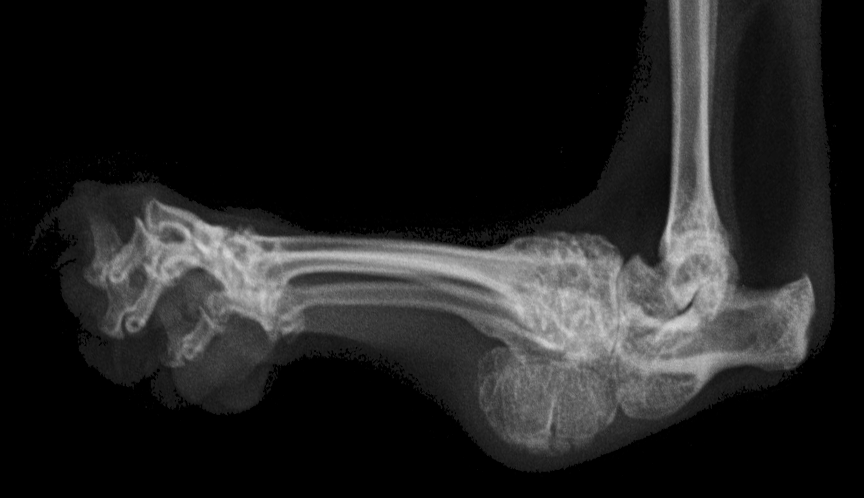

Exemplarisch wird der Fall einer Katze geschildert, die mit 24 Monaten zur Strahlentherapie vorgestellt wurde. Die Patientin sei schon immer schlecht gelaufen, mit Meloxicam als Bedarfsmedikation im Haus allerdings gut zurechtgekommen und habe den Wohnraum auf mehreren Ebenen genutzt. Das Springen auf Kratzbaum und Regale sei regelmäßig üblich gewesen. Innerhalb der vier Monate vor Erstvorstellung sei allerdings eine zunehmende Verschlechterung festzustellen, die trotz einer Erhöhung der Schmerzmedikation deutliche Auswirkungen hatte. Die Besitzer berichten eine deutlich reduzierte Bewegungsfreude, Sprünge über mehr als 50 cm Höhe seien die Ausnahme. Bei der allgemeinen Untersuchung zeigte sich die Katze ängstlich aber aufmerksam und auch bei der Palpation der Gelenke nicht aggressiv. Die Tarsalgelenke stellten sich klinisch deutlich verdickt dar, subjektiv schienen sie etwas verkürzt und geringgradig rotiert.

Bereits eine Woche nach Ende der Strahlentherapie berichteten die Besitzer von einem Rückgang der Schwellung und besserer Beweglichkeit der Gelenke, ohne dass sich der Bewegungsradius merklich vergrößert hätte. Im Verlauf der nächsten drei Wochen eroberte der Patient die Wohnung wieder auf allen Ebenen und höhere Sprünge wurden beobachtet. Die Bedarfsmedikation wurde zunächst reduziert und im weiteren Verlauf auf Ausnahmesituationen beschränkt. Die allgemeine Aktivität erhöhte sich, für die Besitzer wichtiger Indikator war eine merklich erhöhte Futteraufnahme ohne Gewichtszunahme. Die Einrichtung der Katzenbereiche wurde trotz der verbesserten Allgemeinsituation so gewählt, dass die Katze möglichst nur auf und von moderaten Höhen springt, um Stoßbelastung zu vermeiden. Im weiteren Verlauf bewegte sich die Patientin auch aktiv im Garten.